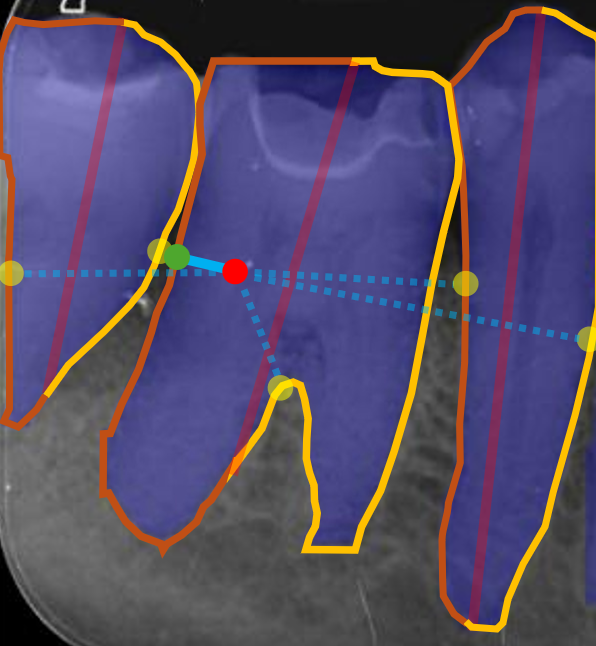

We conducted comprehensive annotation of the collected radiographs, divided into four steps. These include annotating Bone Level Keypoints (BLK) for each tooth, identifying the Teeth Bounding Box (TBB) with tooth orientation, annotating ARR keypoints, and widened PLS bounding boxes. Figure 1 provides visual examples of the annotations.

Refer to caption

Figure 1: Three images containing example annotations of the collected keypoints and rotating bounding boxes.

Bone Level Keypoints (BLK)

The first step involves labelling keypoints relating to the Cementoenamel Junction (CEJ), current Bone Level (BL), and Root Level (RL) on both the mesial (-m) and distal (-d) sides of the teeth. For triple and single-root teeth, a central root level (RL-c) was also included, where single root teeth do not contain RL-m or RL-d keypoints. For multi-root teeth, additional keypoints were annotated to indicate furcation involvement. These included Furcation Apex (FA) and Furcation Bone Level mesial/distal (FBL-m, FBL-d), to indicate furcation involvement, and Furcation Bone Level Healthy (FBL-H) with FA, to indicate a healthy furcation area. FBL-h keypoints are not used by the model, but to identify indication of healthy furcation areas by the annotator, if furcation involvement keypoints are lost or missed in the annotation process. These annotations provide crucial information for assessing the extent of bone loss and periodontal disease, aligning the task with a computer vision problem.

Alveolar Ridge Resorption (ARR)

In the ARR annotation step, focus is placed on identifying the areas of Alveolar Ridge Resorption. This involves annotating the current bone level at locations where a tooth is missing and bone resorption has begun. Annotations for ARR are completed as a bounding box indicating the missing tooth area and a keypoint indicating the lowest point of ARR within the localised area of the missing tooth.

Periodontal Ligament Space (PLS)

In this step, areas where the periodontal ligament space had widened were annotated. PLS annotations in this category indicate ligament spaces that have widened from the tooth with a rotating bounding box, serving as indicators of compromised periodontal health rather than a healthy ligament space.

Teeth Bounding Box (TBB)

The final step in the annotation process involved annotating rotating bounding boxes around each tooth. These serve as a reference box for the model detections of BLK locations and facilitates the calculation of bone loss percentages by identifying tooth orientation.